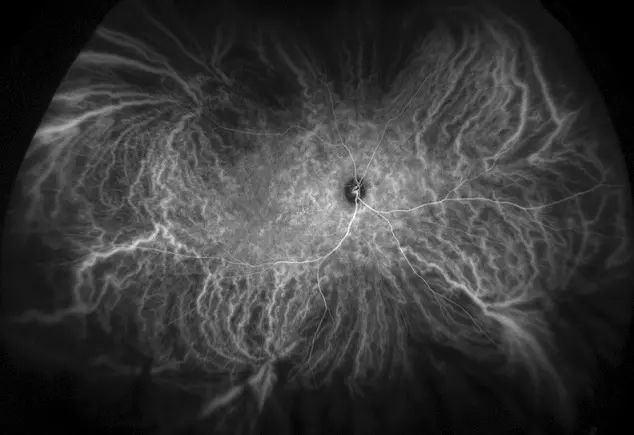

optomap icg

Le laser à balayage comprend l'angiographie au vert d'indocyanine (ICG) ultra-grand champ, une angiographie ultra-haute résolution qui permet une visualisation simultanée du pôle à la périphérie de la rétine. Tout le système vasculaire de la rétine peut ainsi être saisi sur l'image pendant le passage du colorant à l'aide d'une méthode sans contact. Cela aide les professionnels de la vue à diagnostiquer les pathologies oculaires susceptibles d'apparaître en premier lieu dans la périphérie de la rétine, et à mieux traiter les patients.